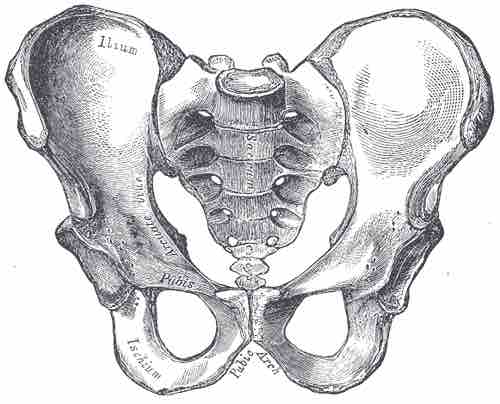

The Male Pelvis

The male pelvis is narrower than that of the female, as can be seen by the less than 90 degree angle of the pubic arch.